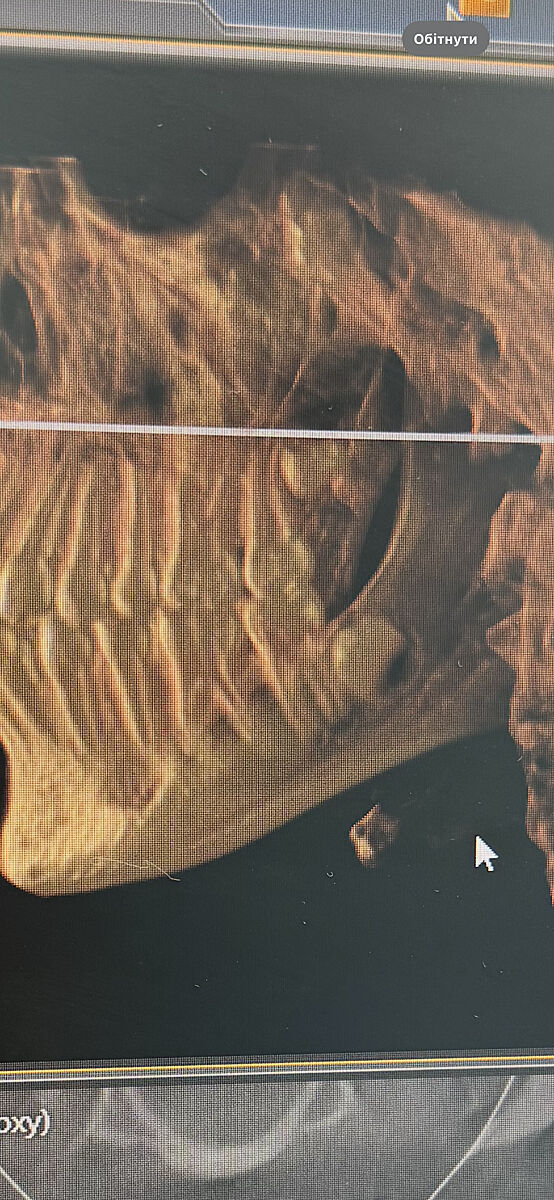

Видаляти зуби мудрості? Фото КТ дитини. Чому ортодонти так хочуть позбутись їх?

В доньки вирівняні зуби брекетами, 14 років

Ортодонт каже треба рвати через 6 міс всі 4 зуба мудрості, поки немає в них коріння, щоб потім не поїхав зубний ряд

Як на мене то верхні зуби ростуть вниз, не заїжджають на сусідні

у вас прямі покази на виривання вони вже прям впираються в зуби

ряд точто поїде як не прибрати